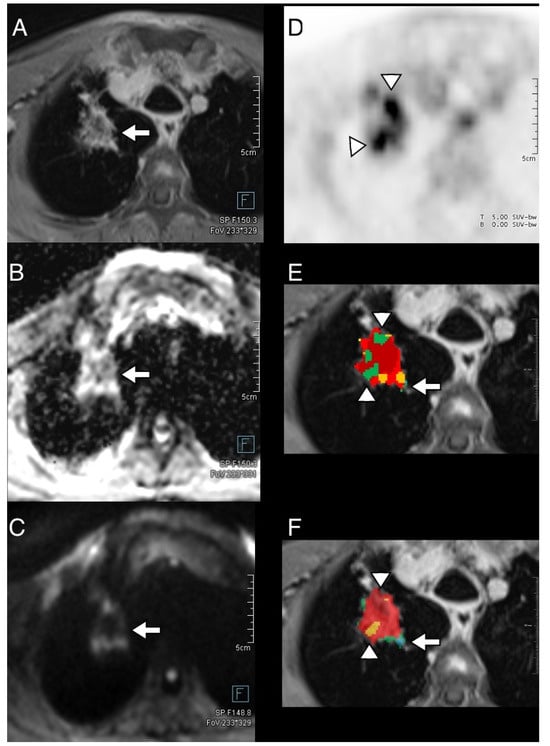

3.4. Thoracic Tumor Segmentation and Registration

3.5. Plausibility of DWI and PET Images